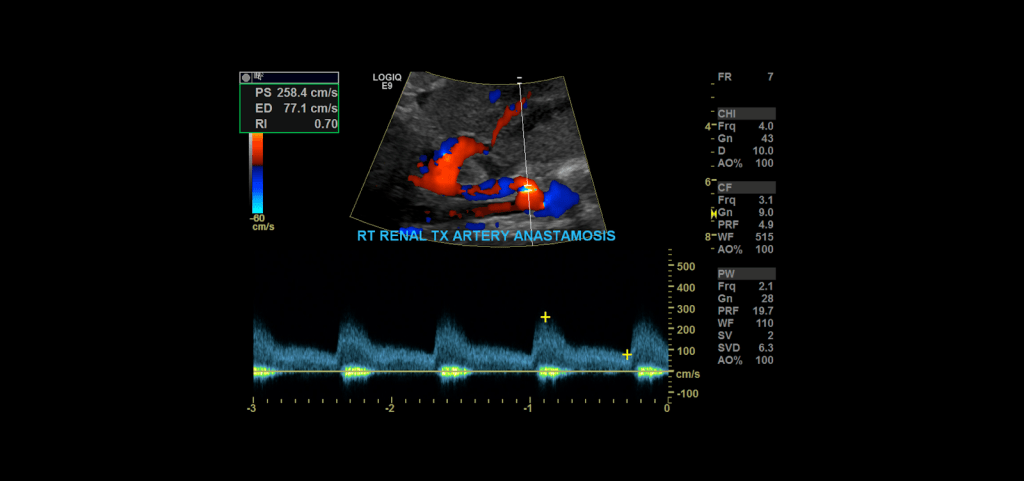

Proceed to doppler the transplant main renal artery and vein. Given the tortuosity sometimes seen in the donor arteries, measuring velocities with angle correction can be tricky. My rule of thumb is that if the artery is perpendicular to the transducer face I don’t use angle correction. If it is parallel to the transducer face I do use angle correction.

Measure the peak systolic and end diastolic velocity. Resistive Index is normally between 0.50 and 0.70. The waveform should be a low resistance waveform with forward flow throughout the cardiac cycle. Take Doppler samples at the anastomosis/proximal section (pay close attention here look for aliasing to detect anastomotic stenosis), the mid and distal portions as well. If there’s any aliasing along the vessel take spectral Doppler samples there too.